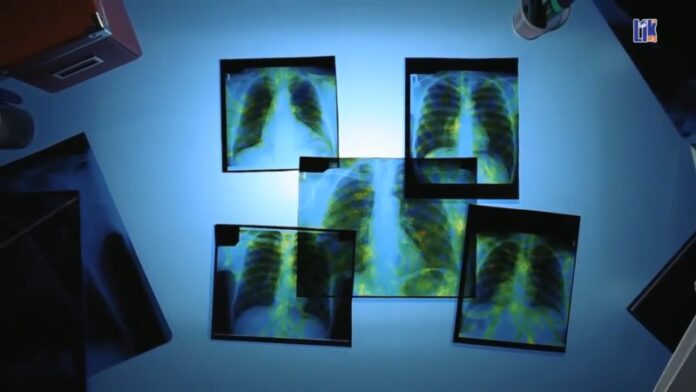

В 2022 году в Рыбнице незначительно снизилась заболеваемость туберкулезом. Об этом говорят статистические данные.

Так, в прошлом году было зарегистрировано 52 новых случая. Это на 5 меньше, чем в 2021 году. Однако немного вырос процент заболеваемости среди детей до 15 лет. В прошлом году в Рыбнице выявили 7 новых случаев туберкулёза у детей. В основном это лёгочная форма, однако встречаются и другие типы болезни, сообщили в Центре гигиены и эпидемиологии.

По словам врачей, во многом выявлению таких скрытых форм способствует повышение уровня диагностики и использование томографа. Эпидемиологи отмечают, что туберкулёз ещё остаётся социальной болезнью, но всё чаще затрагивает иные категории граждан. Этому способствует сниженный иммунитет, нарушение режима сна и питания, стрессовые ситуации.